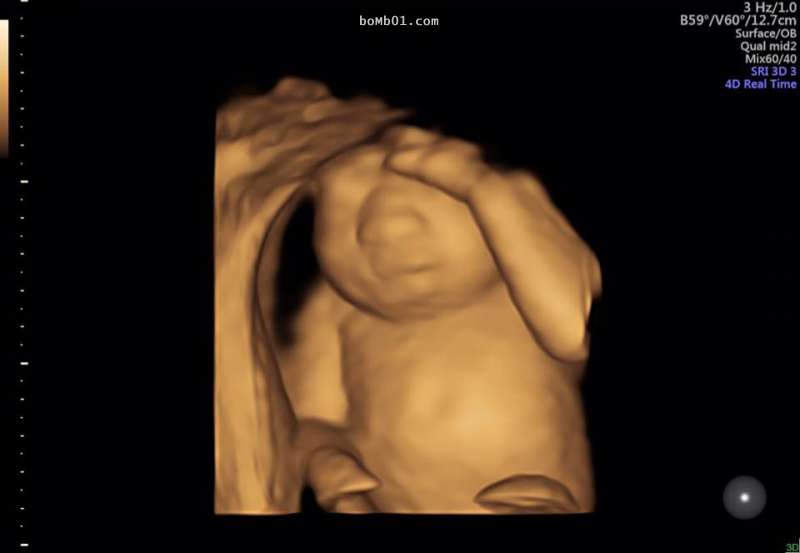

▼原來在寶寶20週的產檢時,醫生發現了她有著明顯的缺陷。這個未出生的女嬰罹患了罕見的「無腦症」,天生缺乏部分的大腦跟顱骨,代表她即使能夠順利生下來,也絕對活不過幾個小時…

▼媽媽克麗在臉書上宣誓了她的決心,「她有著完美的雙腳和雙手,還有完美的腎臟、肺、肝臟…但可惜的是,她並沒有一個完美的大腦,我們最近發現她缺乏腦部,這也意味著她生命的終點。」